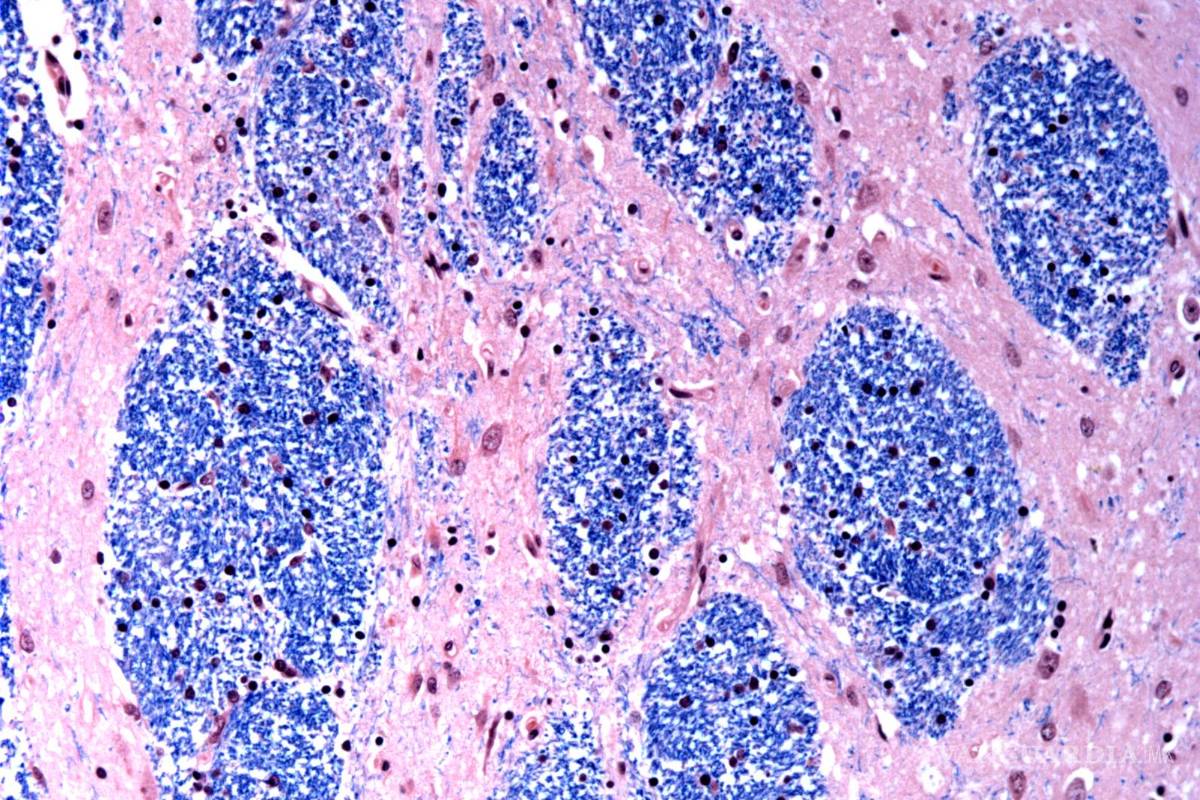

La muerte de las células cerebrales eventualmente conduce a problemas con el movimiento, el pensamiento y el comportamiento. Los síntomas de Huntington, que incluyen movimiento involuntario, marcha inestable, cambios de personalidad y juicio deteriorado, comienzan típicamente entre los 30 y 50 años, empeorando gradualmente durante 10 a 25 años.

Científicos del Broad Institute de MIT y Harvard, el Hospital McLean en Massachusetts y la Facultad de Medicina de Harvard estudiaron tejido cerebral donado por 53 personas con Huntington y 50 sin ella, analizando medio millón de células.

Se centraron en la mutación de Huntington, que involucra un tramo de ADN en un gen particular donde una secuencia de tres letras, CAG, se repite al menos 40 veces. En personas sin la enfermedad, esta secuencia se repite sólo de 15 a 35 veces. Descubrieron que los tramos de ADN con 40 o más “repeticiones” se expanden con el tiempo hasta que tienen cientos de CAGs. Una vez que los CAGs alcanzan un umbral de aproximadamente 150, ciertos tipos de neuronas enferman y mueren.